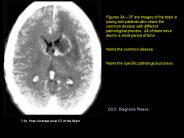

Description: Figures 3A 3F are images of the brain in young sick patients who share the ... All of them have died in a short period of time. Name the common disease. ... – PowerPoint PPT presentation